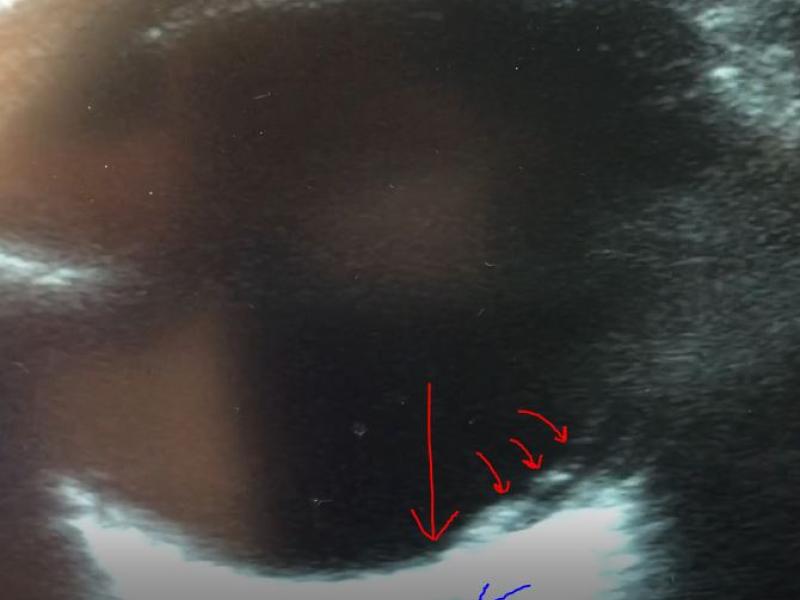

Critical Cases - Painless Vision Loss (With Awesome Eye Ultrasound!)

EM Daily

December 21 2021

Chief Complaint: Vision Loss left eye X 4 days HPI 35 yo